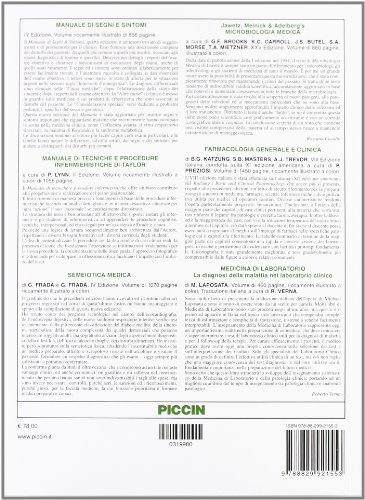

Semeiotica e Metodologia Clinica

Semeiotica e Metodologia Clinica